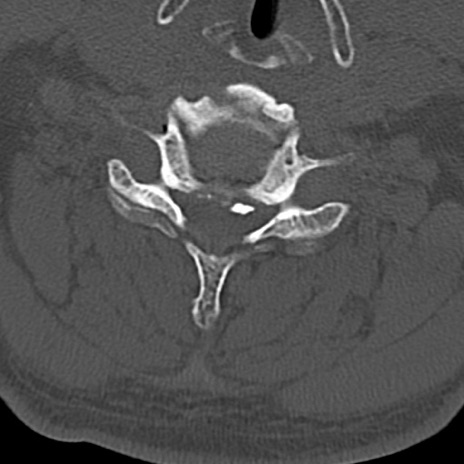

頚椎CT

横断像